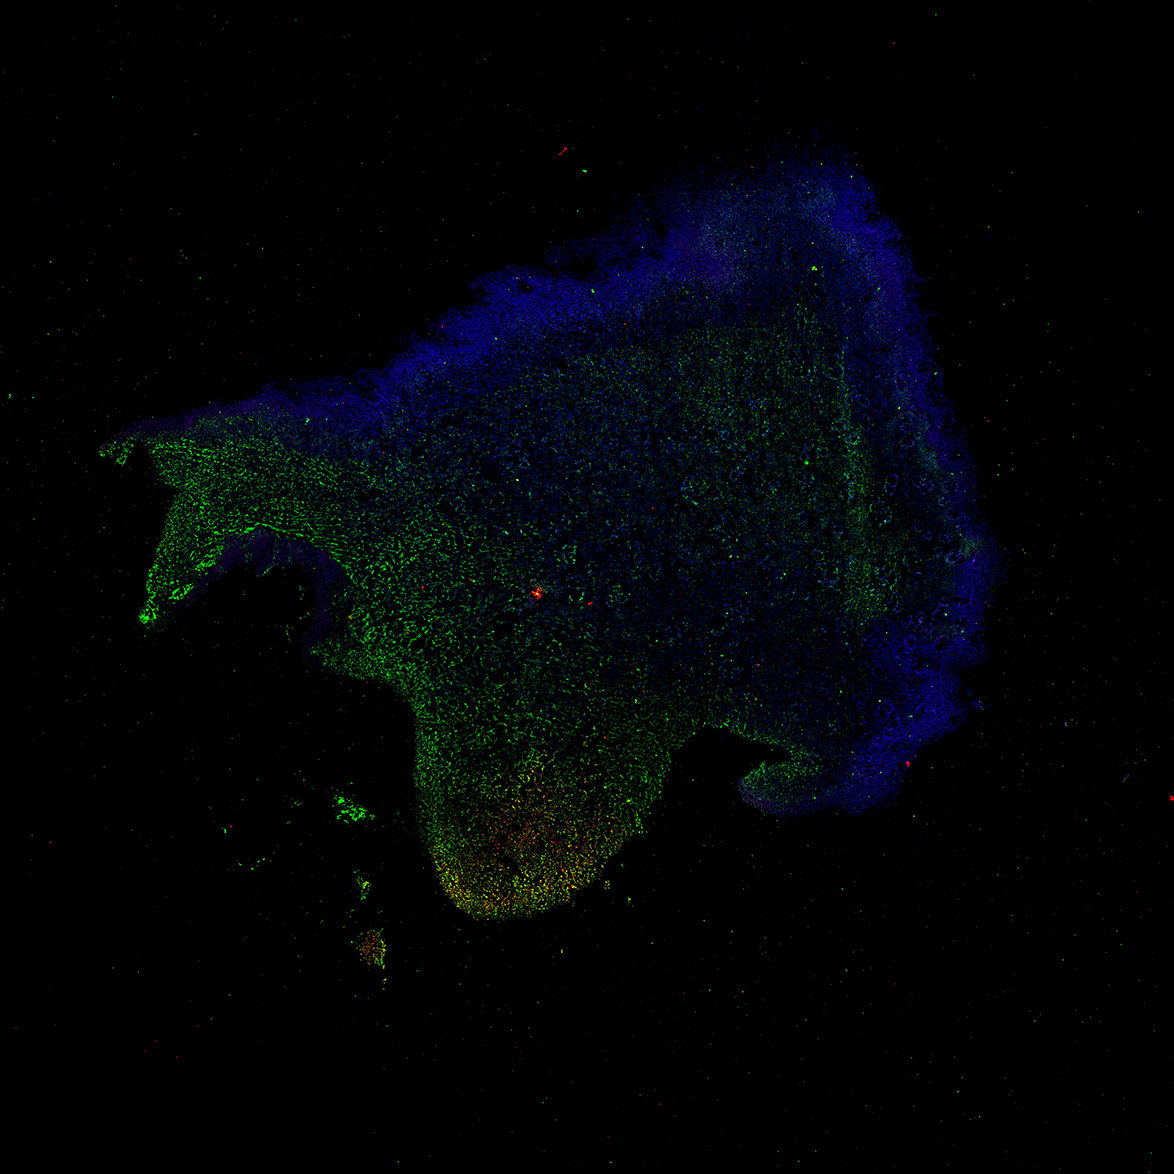

An anatomical analysis of the developing human midbrain from 6 post-conceptional weeks (PCW) to 22 PCW reveals increased tissue complexity, characterized by the emergence of dopaminergic nuclei, as highlighted by immunofluorescence analysis for tyrosine hydroxylase (TH).

13PCW

DAPI

13PCW human midbrain

GFAP

TH

Merged